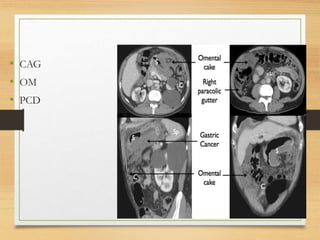

• CAG

• OM

• PCD